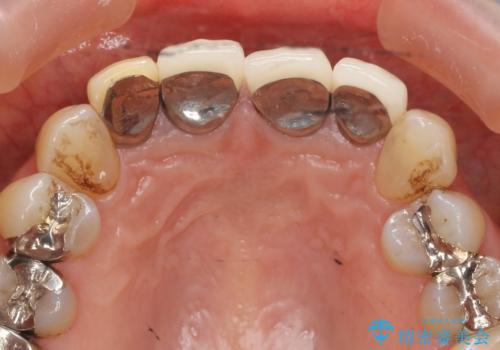

- 以前治療した前歯のセラミックの歯ぐきの位置がかわってしまい境目の変色の改善を希望して来院されました。

大きな穿孔が見られた、右上側切歯の抜去をこないブリッジの設計を含めた前歯の審美性の改善を目的とするセラミック治療を行いました。